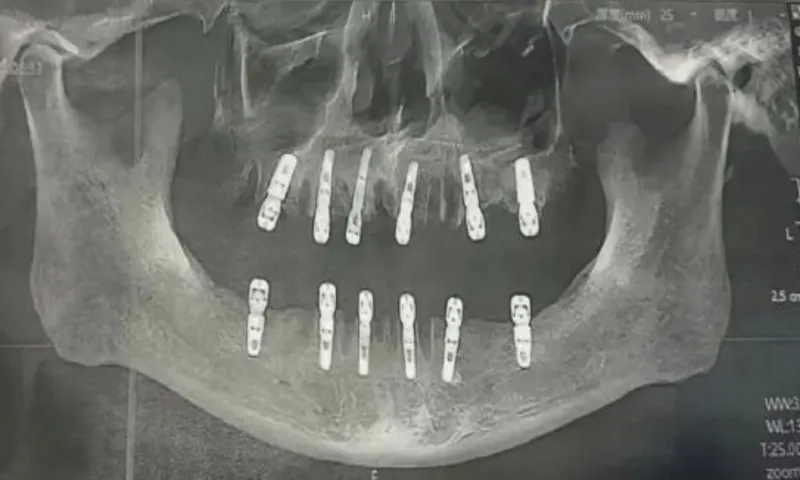

Theo bằng chứng của cô Shu, cha cô đã nhổ 23 chiếc răng và trồng 12 chiếc răng mới trong cùng một lần. Cô Shu cho rằng chính điều này là nguyên nhân khiến cha cô tử vong 13 ngày sau đó.

Theo cam kết chấp thuận thực hiện thủ thuật của bệnh nhân, cha của cô Shu thực tế đã nhổ 23 chiếc răng tự nhiên trước khi khoan 12 lỗ vào hộp sọ và xương hàm để trồng những chiếc răng mới. Tất cả những thủ thuật này được thực hiện trong cùng một ngày. Điều đó có nghĩa là ông đã phải chịu đựng cơn đau không thể tưởng tượng được sau khi thuốc gây mê hết tác dụng.